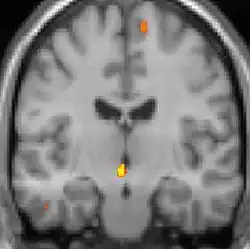

| Diese PET des Gehirns überlagert mit einer Kernspintomographie zeigt eine erhöhte Aktivität in der Schmerzmatrix und im Hypothalamus rechts | ||

Die Positronen-Emissions-Tomographie (PET)-Darstellungen oben zeigen die funktionellen Daten, also die Bereiche, welche bei Schmerzen Aktivität aufweisen, im Vergleich zum Aussehen bei einem schmerzfreien Intervall. Man sieht die sog. Schmerzmatrix, die immer bei Schmerz aktiviert ist und das Areal in der Mitte (in allen drei Ebenen), welches spezifisch im Cluster-Kopfschmerz aktiviert ist. Die VBM Bilder unten zeigen die strukturellen Daten. Hier wird untersucht, ob die Gehirne von Cluster-Kopfschmerz-Patienten anders sind als die Gehirne von Menschen ohne Kopfschmerzen. Nur ein Areal ist anders, da es mehr Graue Substanz enthält: Dieses entspricht dem oben gezeigten funktionellen Areal. Es handelt sich um den Hypothalamus. Dort wird unter anderem der Schlaf-Wach-Rhythmus generiert. Man vermutet daher den Motor des Cluster-Kopfschmerzes im Hypothalamus.[27][28] Mit der 1H-Magnetresonanzspektroskopie konnten auch biochemische Unterschiede zwischen dem Hypothalamus gesunder Menschen und dem Hypothalamus von Cluster-Kopfschmerz-Patienten nachgewiesen werden.[29][30]